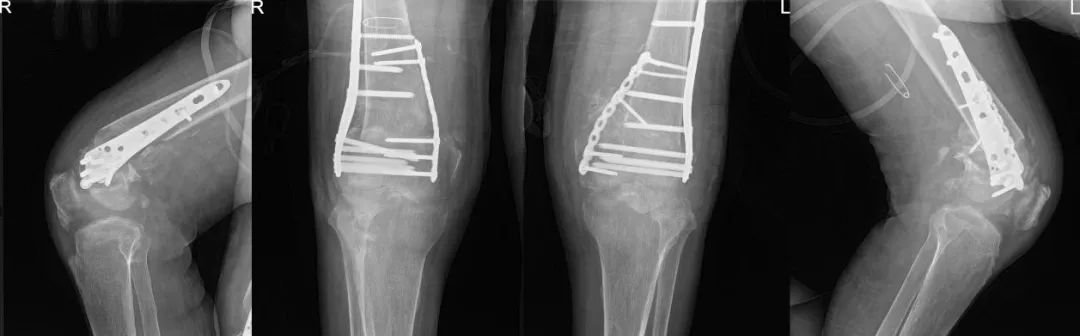

术后X线:双侧膝关节结构恢复

辜先生住进同济医院骨科创伤病区后,樊健组织了科内讨论,对手术入路、固定方式、可能出现的并发症、应急方案及预期效果都进行了明确,家属也给予了充分的理解及支持。近日,经过充分的术前准备,在麻醉科执行主任刘健慧、副主任医师杨君君及手术室护理单元护士长姚英等人的通力配合,并采取有效措施拮抗呼衰等高风险情况下,樊健和主治医师姜超基于前期充分准备,使用手术导板等辅助工具,以最快速度、最小损伤完成截骨、对线、有效内固定等手术操作,重新恢复双侧患膝关节解剖。术后经过重症医学科副主任(主持工作)张磊等监护治疗后,辜先生不久即回到了骨科普通病房,姜超及骨科康复高翔医生等随即来到床边进行康复指导。当看到自己双侧膝关节恢复到正常位、想到日后又能站立时,辜先生及家属激动万分。